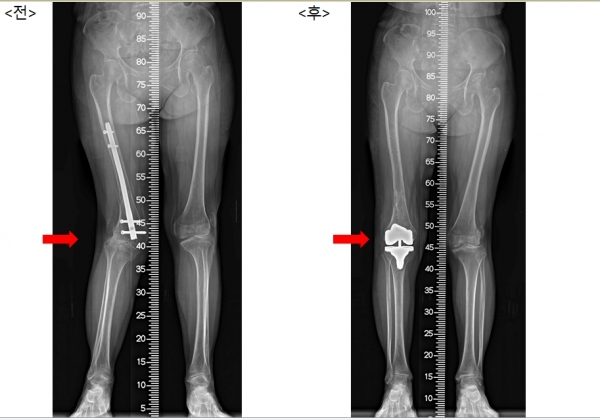

충남 당진에 사는 박영순(가명·62세, 여)씨는 선천적으로 무릎뼈(슬개골)가 정상위치를 벗어나 바깥으로 완전히 탈구된 상태로 지내왔다. 10살 때부터는 제대로 걸을 수 없게 되었고, 성인이 되어 수도권 대형병원을 비롯해 전국의 병원을 다니며 치료 가능성에 대해 확인했지만 늘 돌아오는 답변은 ‘치료가 어렵다’는 것이었다.

설상가상으로 수년 전 낙상으로 인한 대퇴골 골절상까지 입어 수술을 받았지만 아랫다리가 뒤틀리는 변형이 생겼고, 박씨를 본 의사들로부터 절뚝거리나마 걷고 있다는 사실이 더 신기하다는 말을 듣기도 했다.

김 교수는 퇴행성 변화가 나타난 관절을 절제하여 인공관절로 대체하고, 탈구된 무릎뼈를 제자리에 위치시키는 수술을 시행했다.

수술은 대성공을 거두었고, 이후 박 씨는 정상인과 가깝게 걸을 수 있게 되자 매우 큰 만족감을 드러냈다.